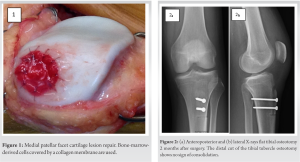

An athletic 24-year-old military man was surgically treated for an unstable and painful patella by performing a flat TTO associated with a medialization and distalization shift. The pre-operative knee injury and osteoarthritis outcome score (KOOS) were 72. The TT–trochlear groove distance (21 mm) and the Caton-Deschamps index (1.24) were normalized by the osteotomy. The chondral lesion present on the medial patellar facet was repaired using bone marrow-derived cells covered by a collagen membrane (Fig. 1). Fixation of the TT was achieved with two lag screws (4.5-mm diameter).

During the 1st month, the knee’s range of motion was gradually recovered, without exceeding 90° flexion. Isotonic knee locking exercises were postponed during 3–4 weeks while isometric contractions were encouraged. On his own initiative, the patient performed multiple isotonic locking exercises and frequent knee extension postures in addition to his rehabilitation program, for several weeks and months after surgery. The evolution was favorable both clinically and radiologically with a comeback to normal knee function at 3 months. However, a consolidation delay of the distal osteotomy cut was observed at 2 months (Fig. 2). 7 months after surgery, while walking around, the patient experienced severe pain at the operation site without sustaining apparent trauma. Weight-bearing was impossible.

An emergency X-ray of the knee confirmed a spontaneous fracture of the proximal tibia below and arising from the TTO site. The fibula remained intact (Fig. 3). A plating osteosynthesis of the proximal tibia was carried out to avoid cast immobilization and to maintain knee’s function (Fig. 4). Weight-bearing was completely prohibited for 8 weeks while the range of motion was gradually recovered and completed after 2 weeks. A removable knee extension splint and 2 crutches protected the osteosynthesis for 8 weeks. Full weight-bearing and normal gait were obtained at 3 months. Both the proximal tibial fracture and the osteotomy distal cut were consolidated at 10 months after plating osteosynthesis (Fig. 4). KOOS score was, at that time, evaluated at 90.5.